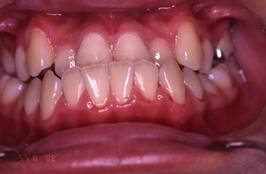

インビザラインによる矯正症例2 22歳女性

治療開始時。正中離開と過蓋咬合がありました

治療途中 5か月後